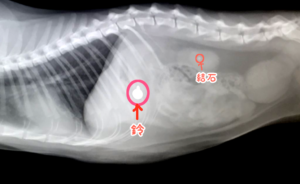

半年前、2022年末の健康診断で全身の超音波検査をした際、胆泥が見つかったテツ子(2016年生まれ雑種猫♀)。

ベジタブルサポートを飲ませて1ヶ月後、再度超音波検査を受けたものの胆泥は相変わらず。

胆泥はご飯の前後などで溜まってたり消えたりするので、もう少し様子を見ても良いとのことで、更に1ヶ月後に再検査。

それでも胆泥は変わらず存在しました。

ウルソを2ヶ月半続けた結果

毎朝ウルソ50mgを1錠、2ヶ月半飲ませ切ったところで再診。

胆泥はきれいに消えていました!